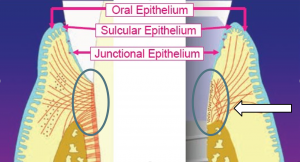

Mielőtt a leírást a második különbség, hogy tisztázni kell egy nagyon fontos pont tekintetében biológiai szélesség (SB).

A „biológiai szélesség” ugyanazt jelenti, mint a fog-fogíny mellékletet. Ahogy közeledik a Apex 3 részből áll:

- Sulkus - sulcus

- epiteliális mellékletet

- kötőszöveti mellékletet

- Kötőszöveti foghoz mutat egy hosszirányú és perpedikulyarno-irányított kollagén rostok. Felhelyezése az implantátum végezzük főleg kollagén rostok párhuzamosan elrendezett az implantátum felületéhez, így eleve kevésbé erősen, mint hogy a fogat.